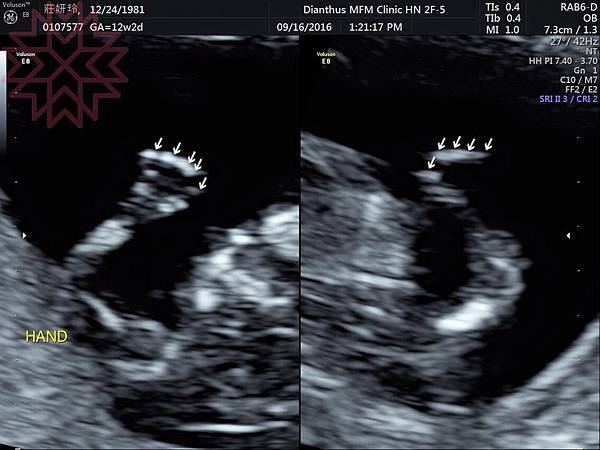

檢驗師才剛稱讚完他躺的位置很正確的下一秒他就開始瘋狂打滾

背對我們或者是用手把臉遮住,照不到鼻樑骨也沒辦法判斷頸部透明帶厚度

幸好這孩子很識相,等醫生來檢查的時候終於躺到正確位置

(紅色虛線的地方就是頸部透明帶)

還獲得看起來很像外星異種的3D影像

醫生有提醒我們不管是3D或是4D都是娛樂用的

想要確認胎兒發育還是要靠2D高層次超音波喔